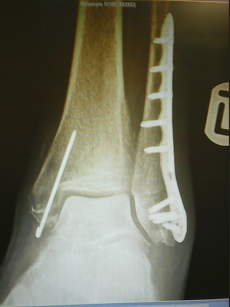

Can I strongly advice that you never descend a staircase without holding onto a banister, not even to test your progress. It’s really not worth the risk! We don’t recover as quickly with age and should you so much as badly sprain or break an ankle, will set back your stroke recovery, undoing a lot of the hard work and progress you have again.

This comes from one knows, and I WAS holding onto the bannister when I did this, could have been a lot worse if I hadn’t.

This was a year before my stroke.